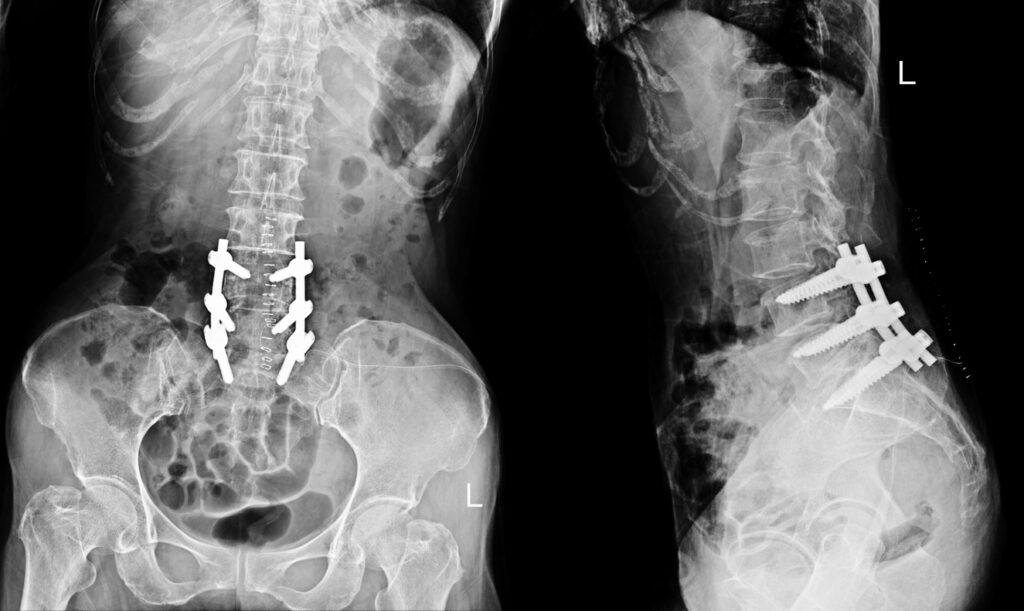

Spinal fusion is often recommended for chronic low back pain, degenerative disc disease, or lumbar instability. While it can be life-changing for some, lumbar fusion is irreversible and carries significant risks—adjacent segment degeneration, reduced mobility, and unpredictable long-term outcomes.